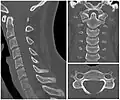

In humans, cervical vertebrae are the smallest of the true vertebrae and can be readily distinguished from those of the thoracic or lumbar regions by the presence of a transverse foramen, an opening in each transverse process, through which the vertebral artery, vertebral veins, and inferior cervical ganglion pass. The remainder of this article focuses on human anatomy.

By convention, the cervical vertebrae are numbered, with the first one (C1) closest to the skull and higher numbered vertebrae (C2–C7) proceeding away from the skull and down the spine. The general characteristics of the third through sixth cervical vertebrae are described here. The first, second, and seventh vertebrae are extraordinary, and are detailed later.